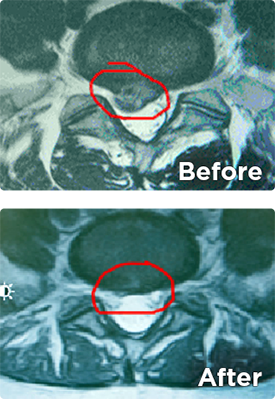

Images below display a herniated disc before and afterthe NDS method treatment.

Herniated Disc x-ray